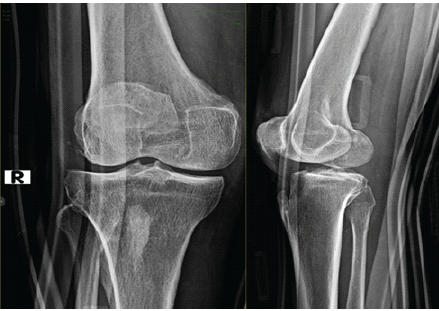

Radiographs of the knee revealed increased medial joint opening with respect to the normal knee joint. (Fig. 1) Local examination of right knee showed increased medial joint space opening with positive valgus stress and posterior sag signs, suggestive of MCL and PCL injuries (Fig. 2).

Figure 1: Pre-operative X-ray of right knee showing increased medial joint space opening.